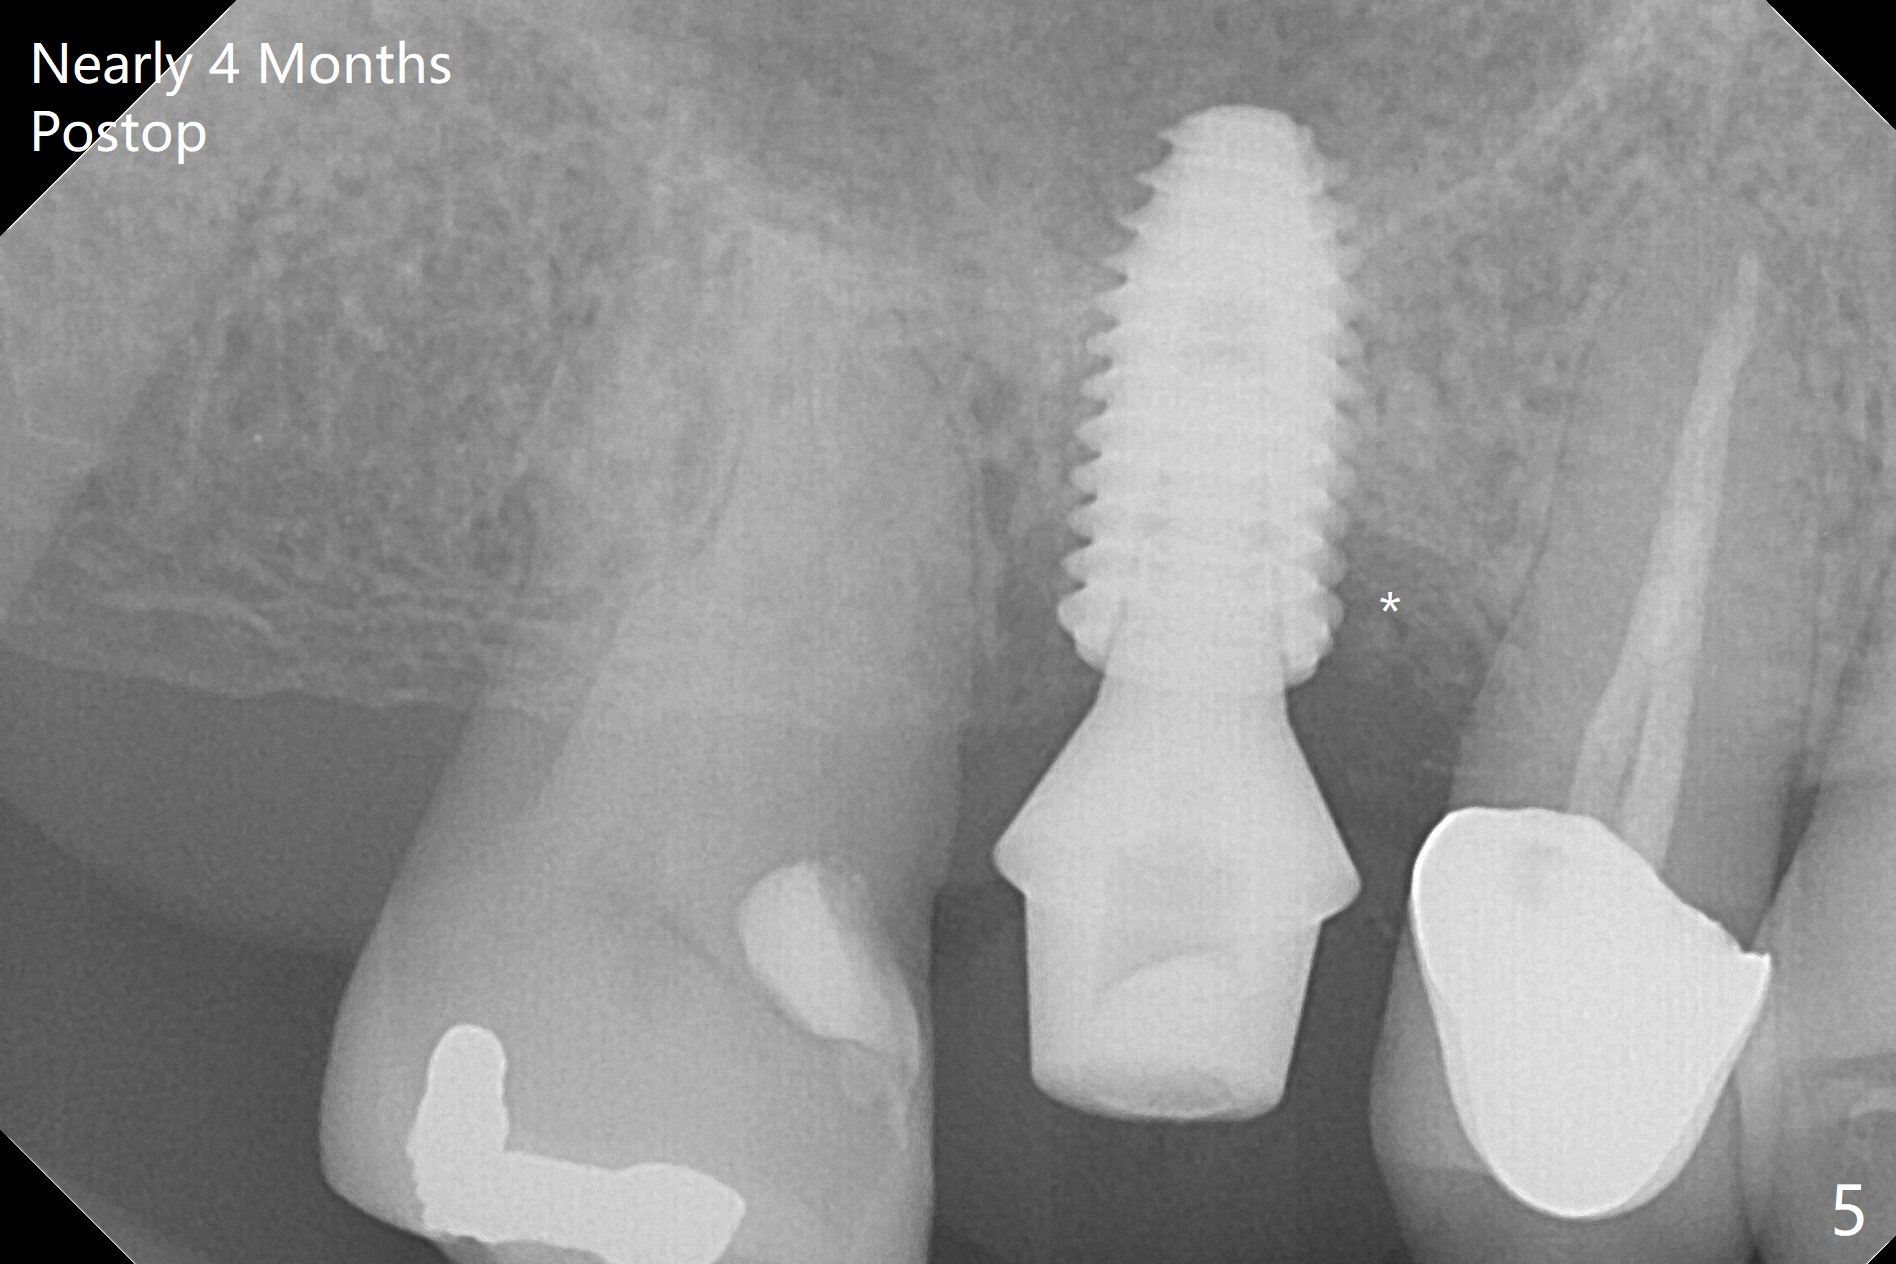

A 5x10 mm implant is placed at #3 according to drill sequence except 4.5x10 mm drill having to be used (plan: underdrilling using 4.0x10 mm as the last one) because of dense bone. Insertion torque is >50 Ncm. Although the implant apparently penetrates the sinus floor (Fig.1), the bottom of the osteotomy is intact before implant placement. In addition, the 12 mm bone trimmer does not touch the septal bone, while 2.2x8.5 mm drill starting to remove bone. In spite of using the largest cementation abutment (6.5 mm), the buccal (Fig.2) and palatal sockets with bone graft (*) are exposed. An immediate provisional (Fig.3 P) is fabricated for remaining socket closure. The buccal gingiva appears to have receded relative to the abutment margin nearly 4 months postop (Fig.4). The mesial crestal bone defect seems to be repairing (Fig.5 (*),6). The abutment later changes to a 5.7x5.5(2) mm one with margin modification buccomesiolingually before impression.